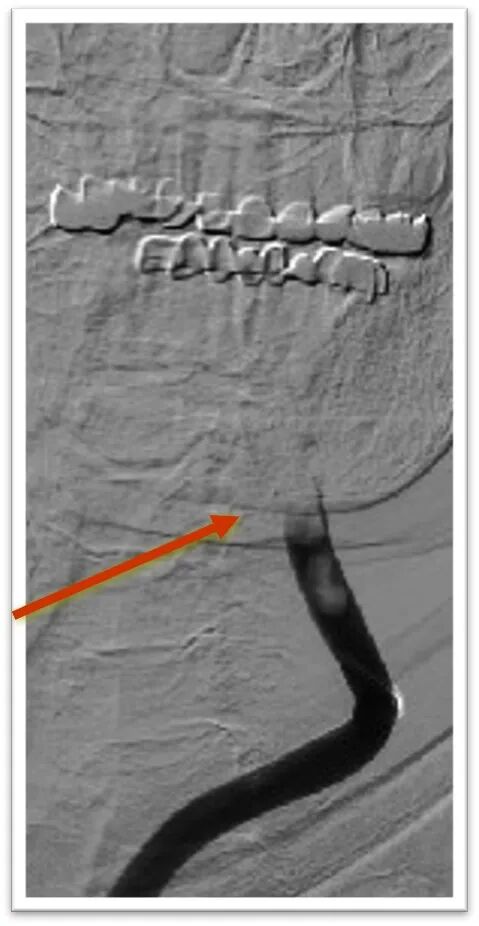

该患者胸主动脉迂曲,主动脉弓呈牛角弓,选择5F 125cm蒸汽塑形后在泥鳅导丝引导下同轴引导6F Neuron Max长鞘顺利置于左侧颈总动脉;

同轴技术建立良好通道